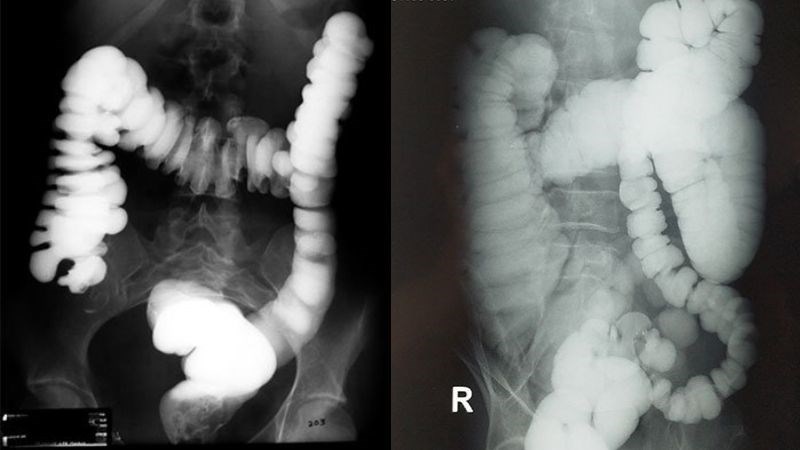

- Chụp X-quang: để xem ruột của trẻ có bị tắc nghẽn không. Bác sĩ cũng có thể sử dụng thêm thuốc cản quang để hình ảnh được rõ nét và chính xác hơn.

-800x450-1.jpg)

Chụp X-quang có thuốc cản quang giúp quan sát rõ hơn ruột bị tắc